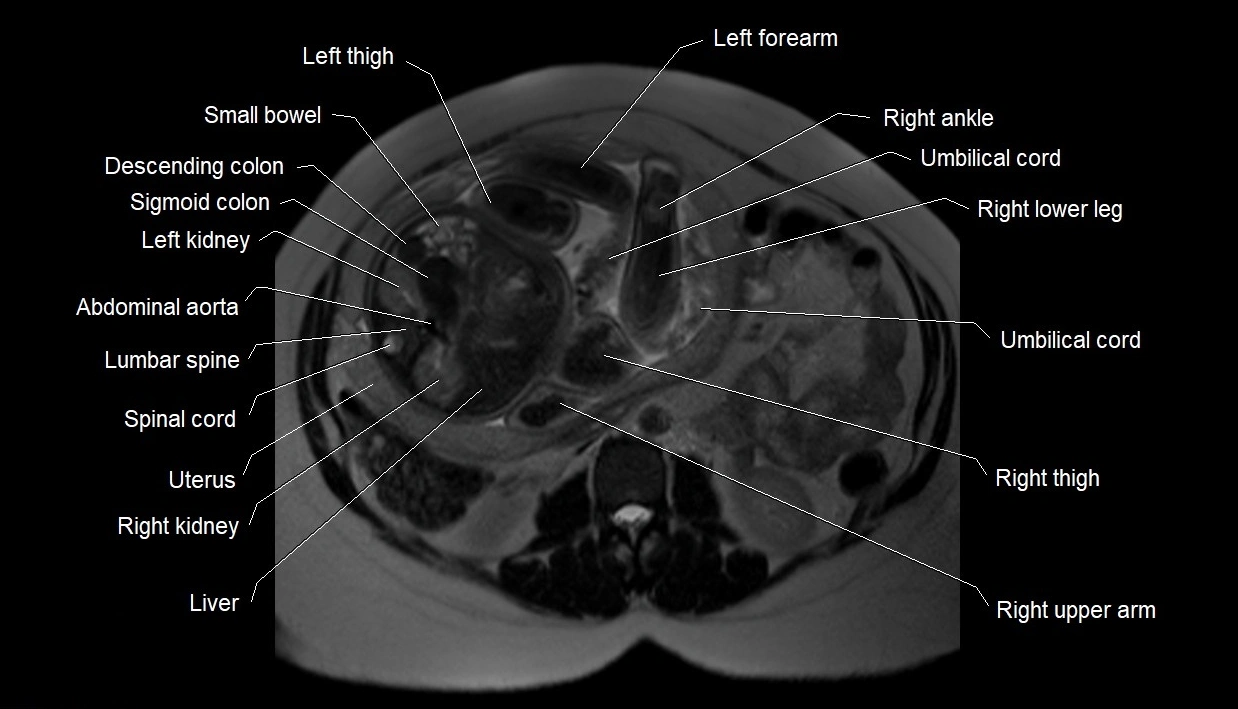

MRI Appearance

T2 HASTE (T2 GRE):

• Amniotic fluid shows very bright hyperintense signal

• Provides natural contrast against fetus and placenta

• Small particles (vernix) may appear as scattered hypointense foci within bright fluid

T1 GRE:

• Amniotic fluid shows low signal intensity (dark)

• Hemorrhage, infection, or proteinaceous content may cause focal or diffuse high signal intensity